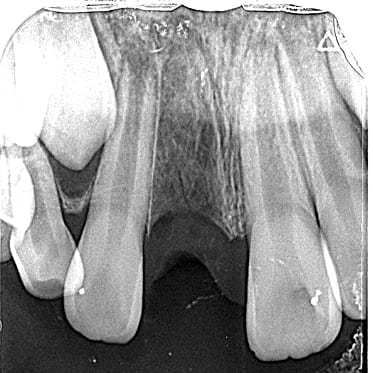

● 先天性の萌出方向異常を部分矯正で治療

藤沢デンタルオフィスの虫歯や破折で先天性の萌出方向異常を部分矯正で治療

01

02

03

04

05

06